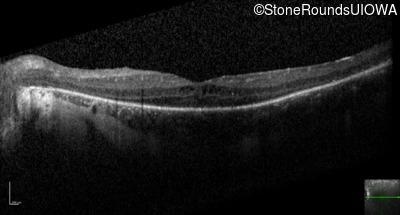

Optical Coherence Tomography - Left - 20/50

Exemplar / OCT Stack